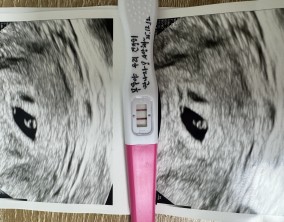

두 줄에서 심장소리까지, 따뜻하게 이어진 시간

이예흔 원장님을 비롯해 의료진과 선생님들 모두 친절하게 대해주셨고, 병원 전체 분위기도 따뜻해서 치료를 받는 동안 마음이 한결 편안했습니다. 그런 환경 덕분에 끝까지 치…